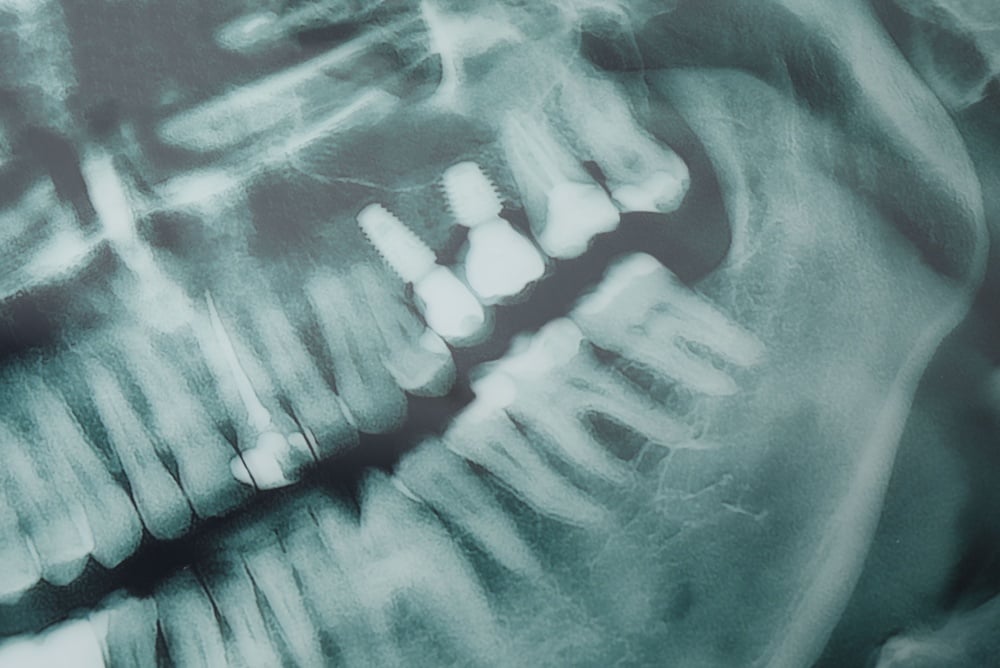

Dental implants replace missing teeth by anchoring an artificial tooth root into the jaw. This guide explains how to choose the best implants for teeth in Greenacres, FL and elsewhere, covering implant types, materials, digital tech, who’s a good candidate, costs, and next steps so you can make an informed choice with your dentist.

Endosteal implants are the standard screw or tapered posts placed directly into the jawbone. They’re the most common choice for single-tooth replacements and multi-tooth cases because they offer strong support for crowns and bridges and predictable long-term results.

3D imaging and digital planning

CBCT scans and facial scanning show bone volume and soft tissue in 3D. Digital planning pinpoints implant size, angle, and position to avoid nerves and sinuses and to optimize esthetics and function before surgery.